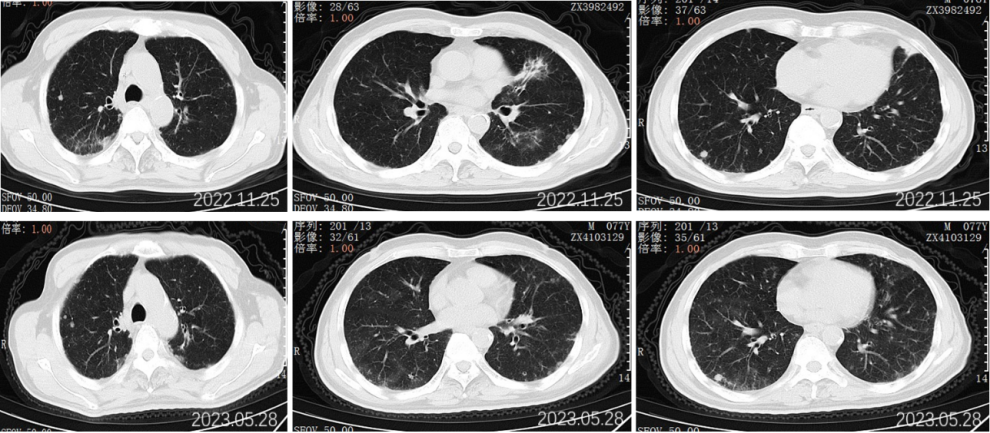

2022.11.25胸部CT平扫:对比2022-09-27影像:1.新见两肺多发间质性肺炎样改变,感染考虑,VP-RADS 2类;2.两肺多发小结节、类结节影,部分较前略缩小,转移性考虑;3.左侧第5后肋骨质破坏,相仿。

2023.5.28胸部CT平扫:对比2022-11-25片:1.两肺散在多发炎症,较前相仿,VP-RADS 2类;2.两肺多发小结节、类结节影,转移瘤考虑,较前相仿;3.左侧第5后肋骨质异常,相仿。男性乳腺发育。

2023.09.29胸部CT平扫:对比2023-05-28片:1.两肺多发小结节、类结节影,较前增多增大,转移瘤考虑。2.两肺散在多发炎症,部分较前吸收;3.左侧第5后肋骨质异常,相仿;4.右侧胸腔少量积液。男性乳腺发育。